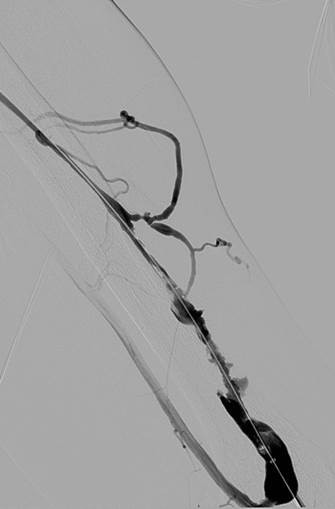

Fistulogram demonstrating thrombotic occlusion of a left brachiocephalic AV fistula (Note: arterial reflux of contrast).

Post 1st pass with AngioJet DVX Catheter (no thrombolytics used).

Post 2nd pass with DVX Catheter and balloon angioplasty of underlying stenosis. No impedance to forward flow in AVF.

Once forward flow is established and stenosis treated, the residual thrombus should resolve.